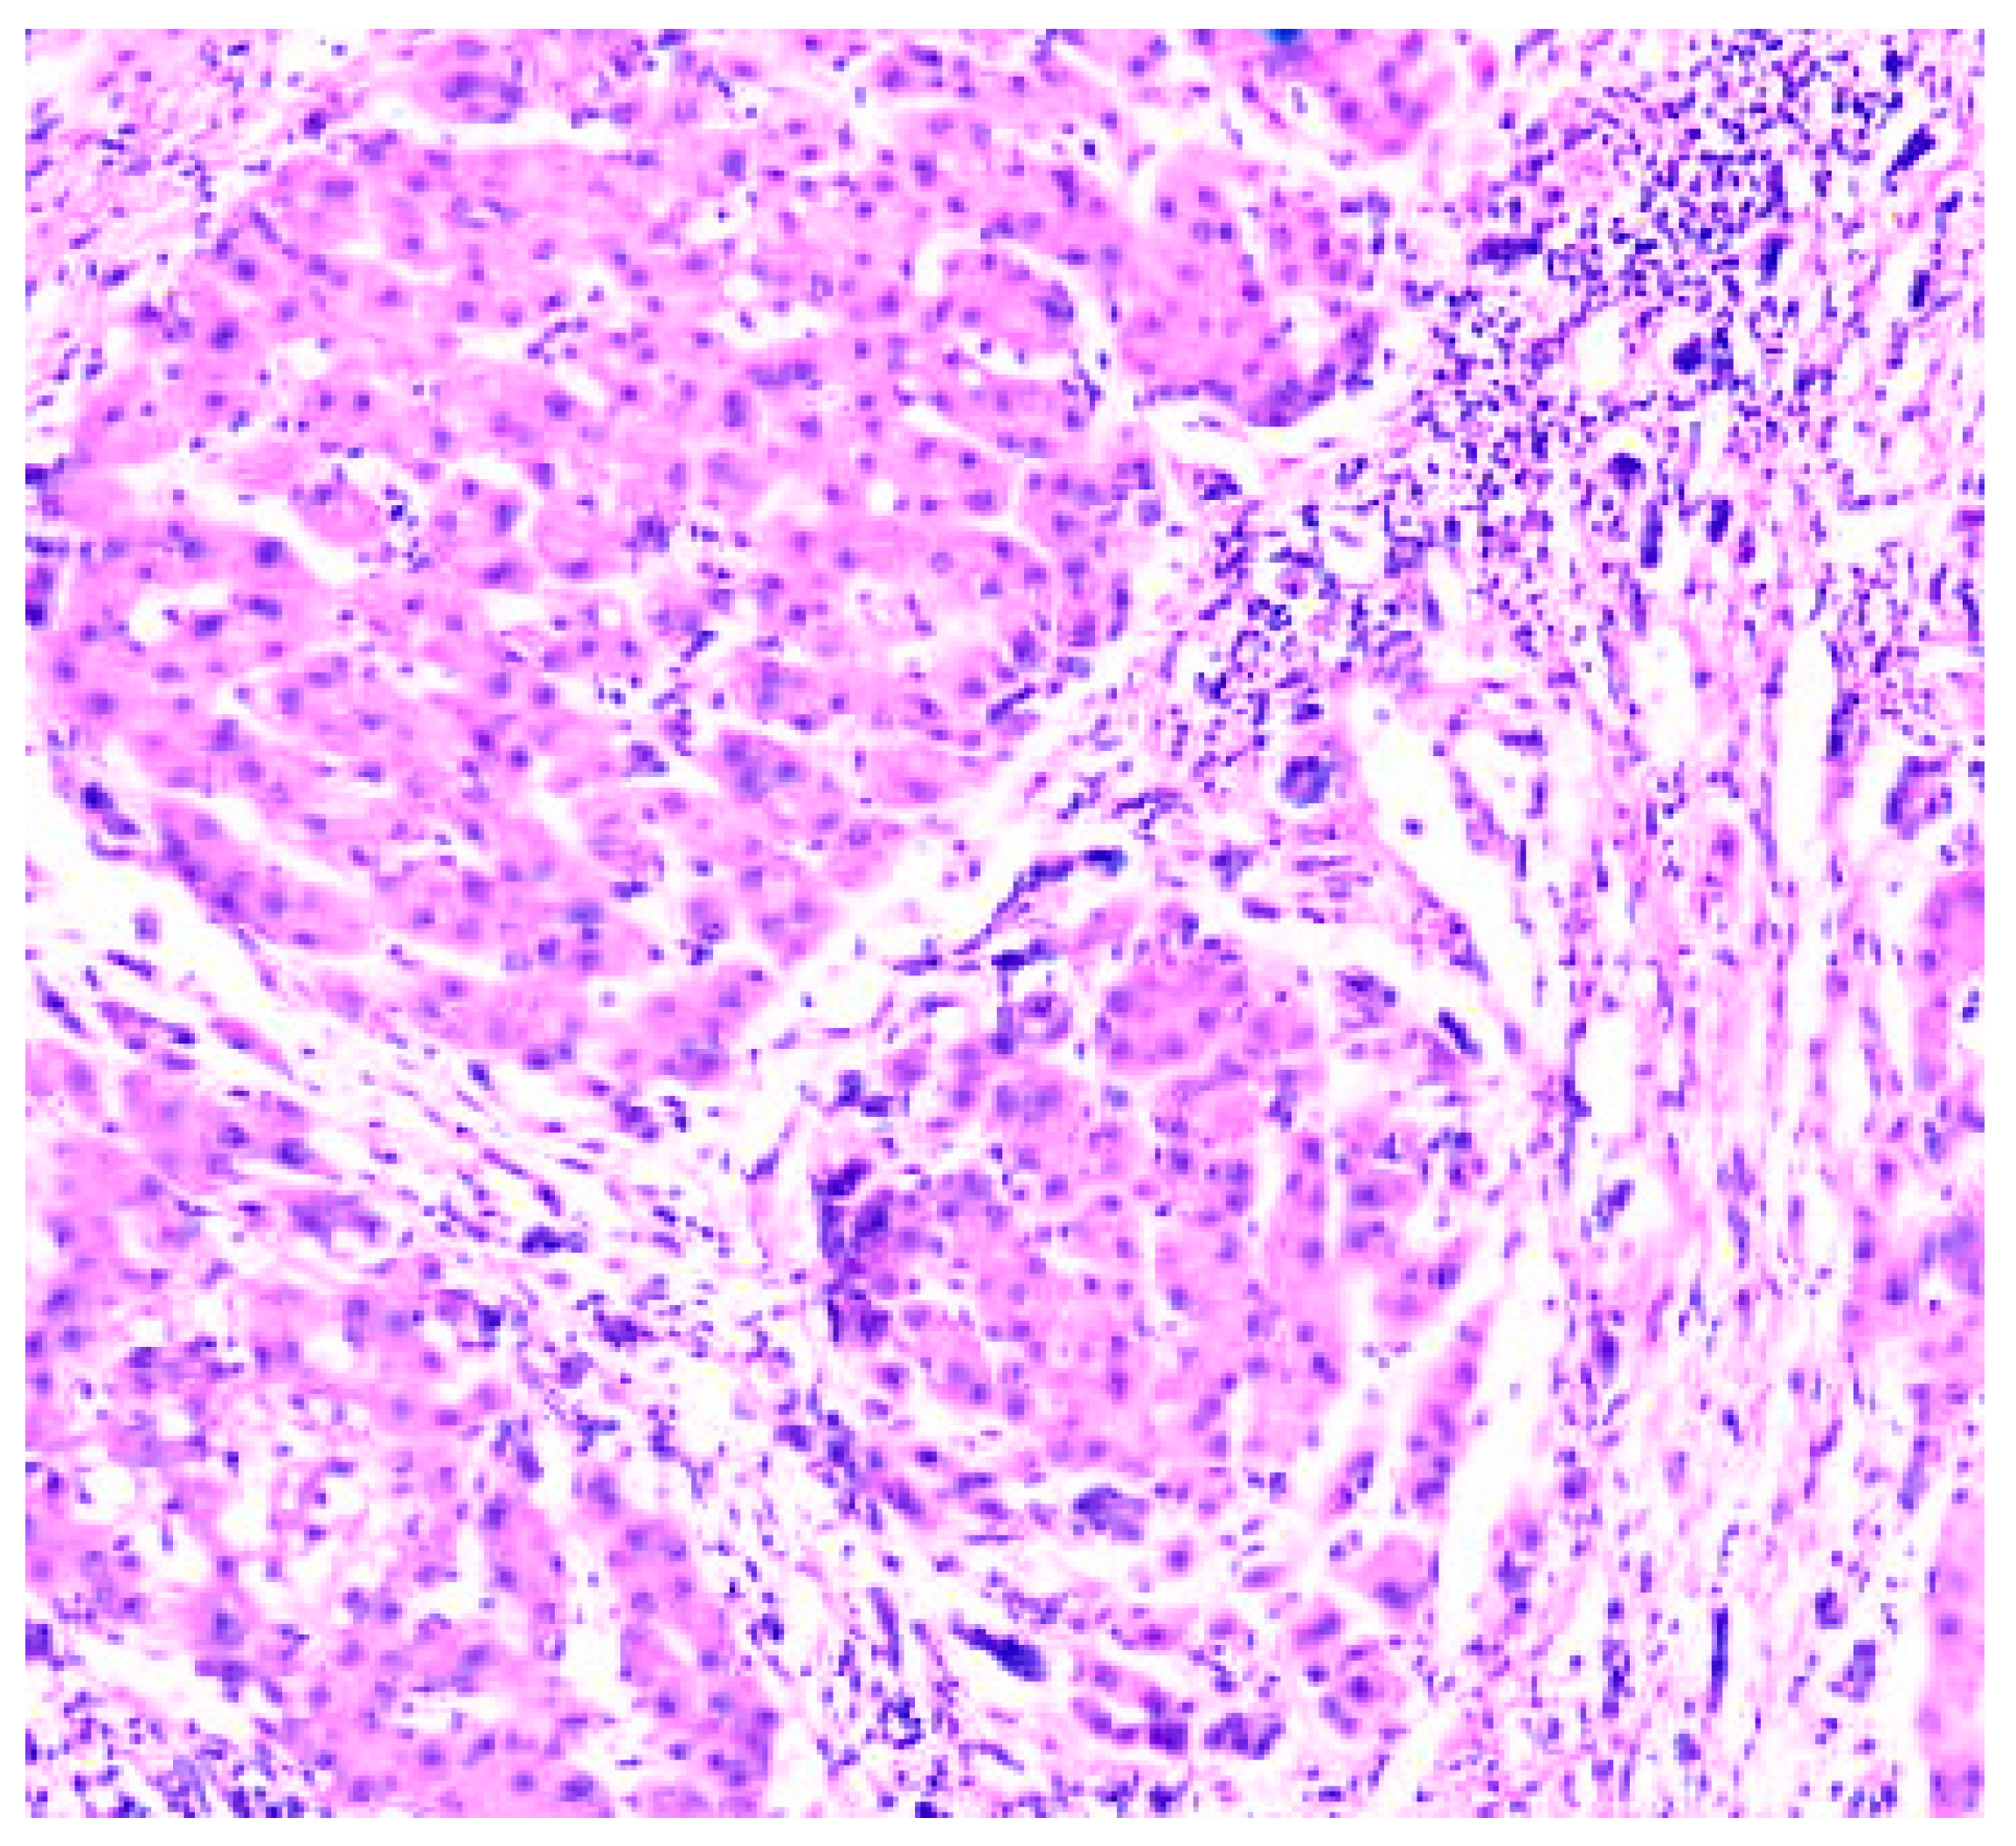

Figure 5. Cirrhosis liver x10 H&E stain.

Figure 6. Cirrhosis liver x10 H&E stain.